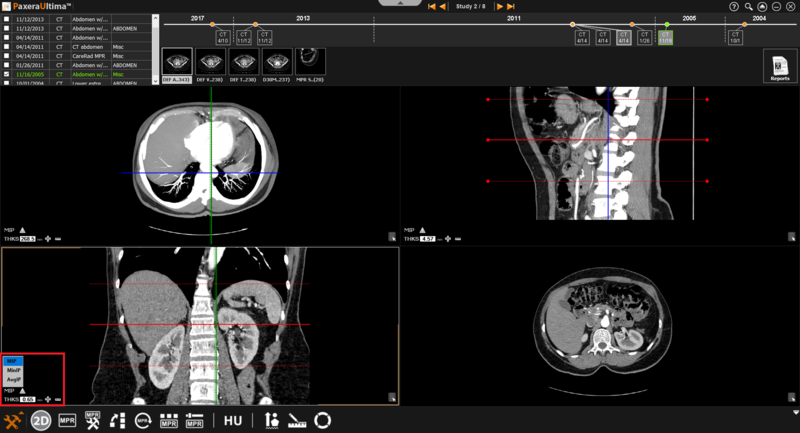

9.4.2. Normal Mode

The normal MPR mode provides three views of the images as shown below:

» Adjust line position - The positions of the lines can be adjusted by clicking on the line of interest and dragging it in the direction of interest.